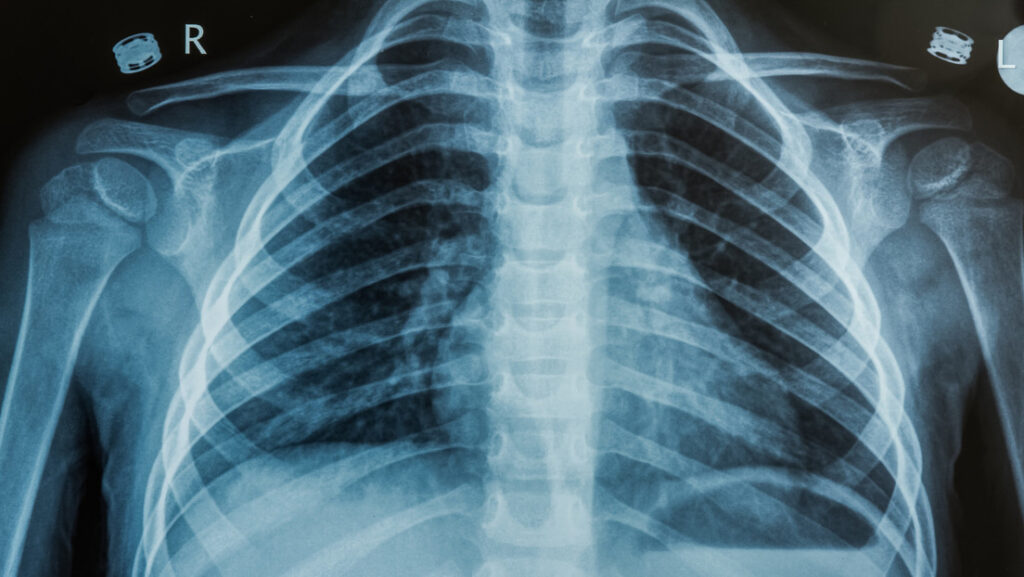

El hombre se había estado automedicando con medicinas de venta libre para la tos, pero, al no ver ninguna mejoría, a inicios de junio, acudió al Departamento de Cirugía Torácica del Hospital de Zhejiang para un chequeo. Una tomografía computarizada reveló una masa de aproximadamente un centímetro de largo dentro de su pulmón derecho, lo que hizo temer que tuviera un tumor maligno.